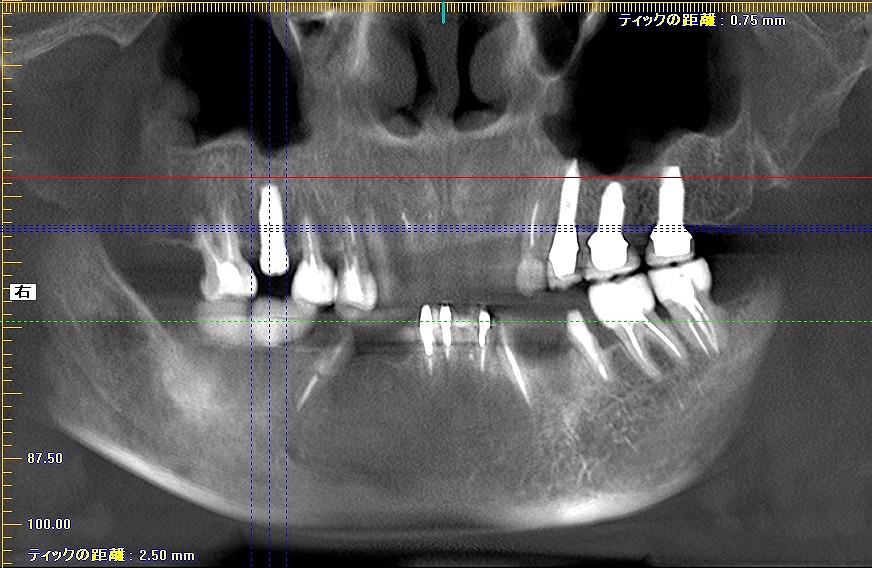

しっかりとしたインプラントが入りました

長さも申し分ないインプラントかと思います